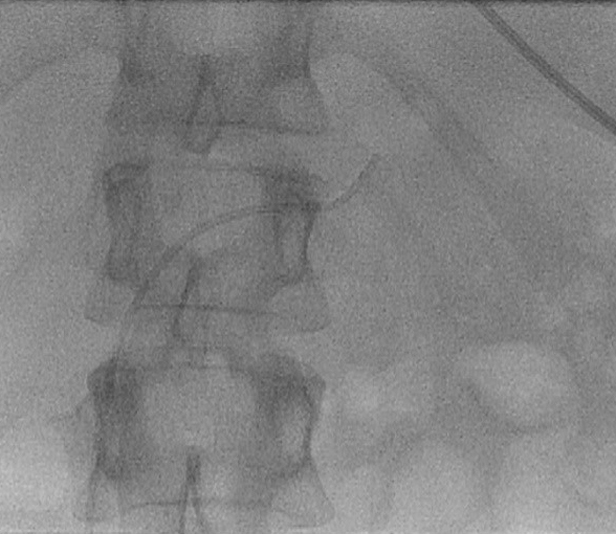

Sondierung einer verengten Stelle der Nierenarterie mit einem Führungsdraht.